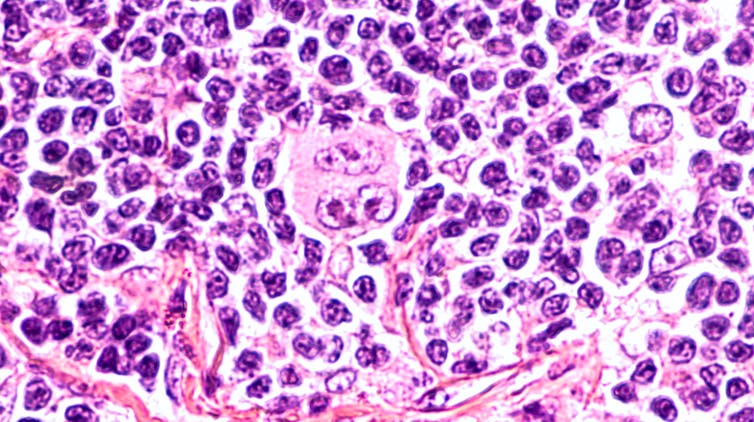

Se acaba de publicar en el British Journal of Haemathology el siguiente caso clínico: Varón de 61 años con inflamación de los ganglios y pérdida de peso, recibía hemodiálisis por insuficiencia renal terminal después de un trasplante renal fallido. Se le diagnostica un linfoma de Hodgkin clásico en estadio III (el linfoma afecta a áreas ganglionares localizadas a ambos lados del diafragma o por encima del diafragma y en el bazo).

Según los autores, la hipótesis es que la infección por SARS-CoV-2 desencadenó una respuesta inmunitaria antitumoral: las citocinas inflamatorias producidas en respuesta a la infección podrían haber activando células T específicas con antígenos tumorales y células asesinas naturales contra el tumor. El SARS-CoV-2 le había curado el linfoma.